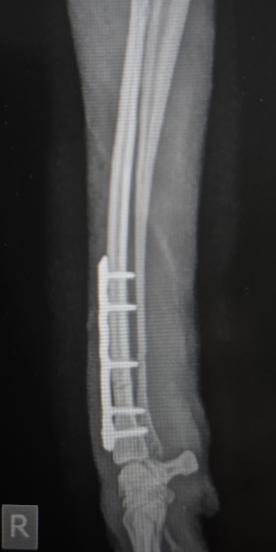

Geschlossene Unterarmfraktur

Postoperatives Röntgenbild: die Fraktur wurde reponiert und mit Platte und Schrauben stabilisiert (Osteosynthese).